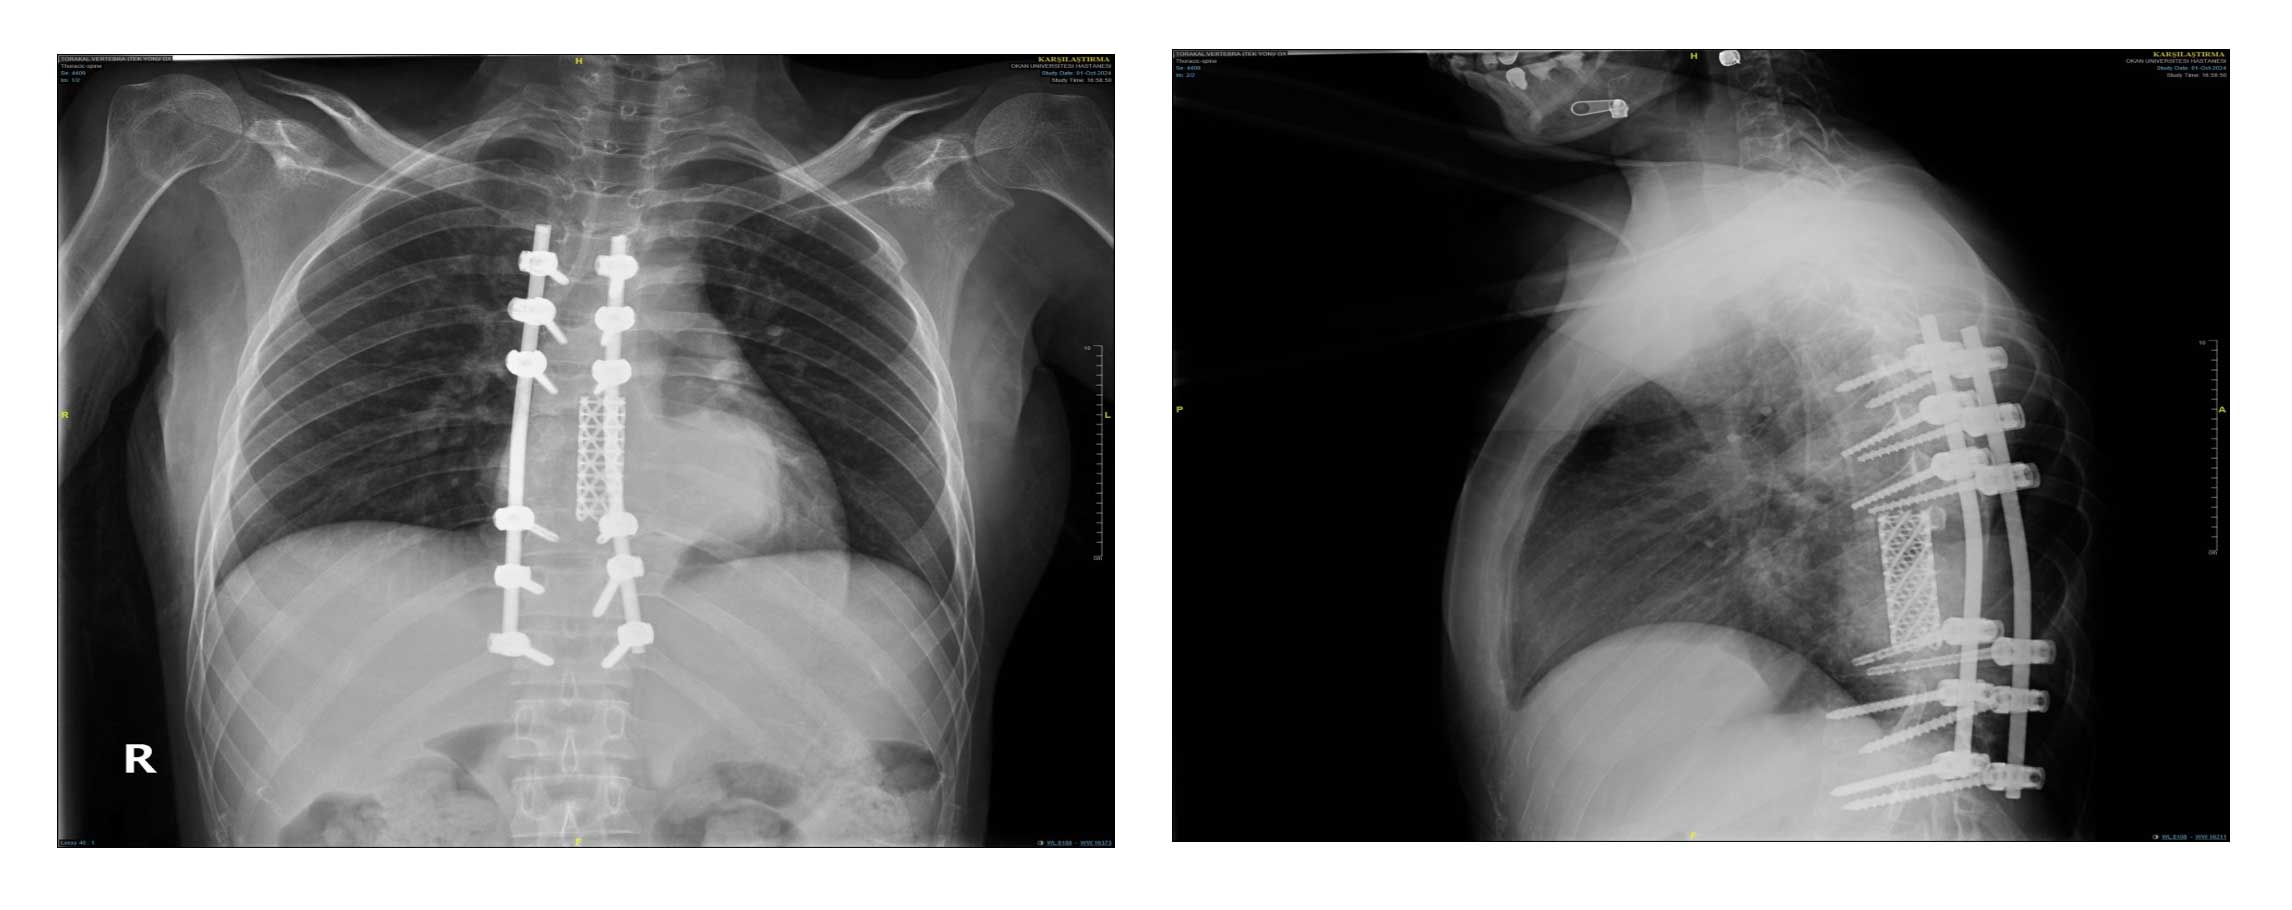

Ameliyat Öncesi: Tomografi kesitlerinde daha önce uygulanan kafes ve enstrümentasyon ile birlikte tümör nüksü görülmekte.

Ameliyat Öncesi: MR’da büyük boyutta tümör nüksü görülmekte.